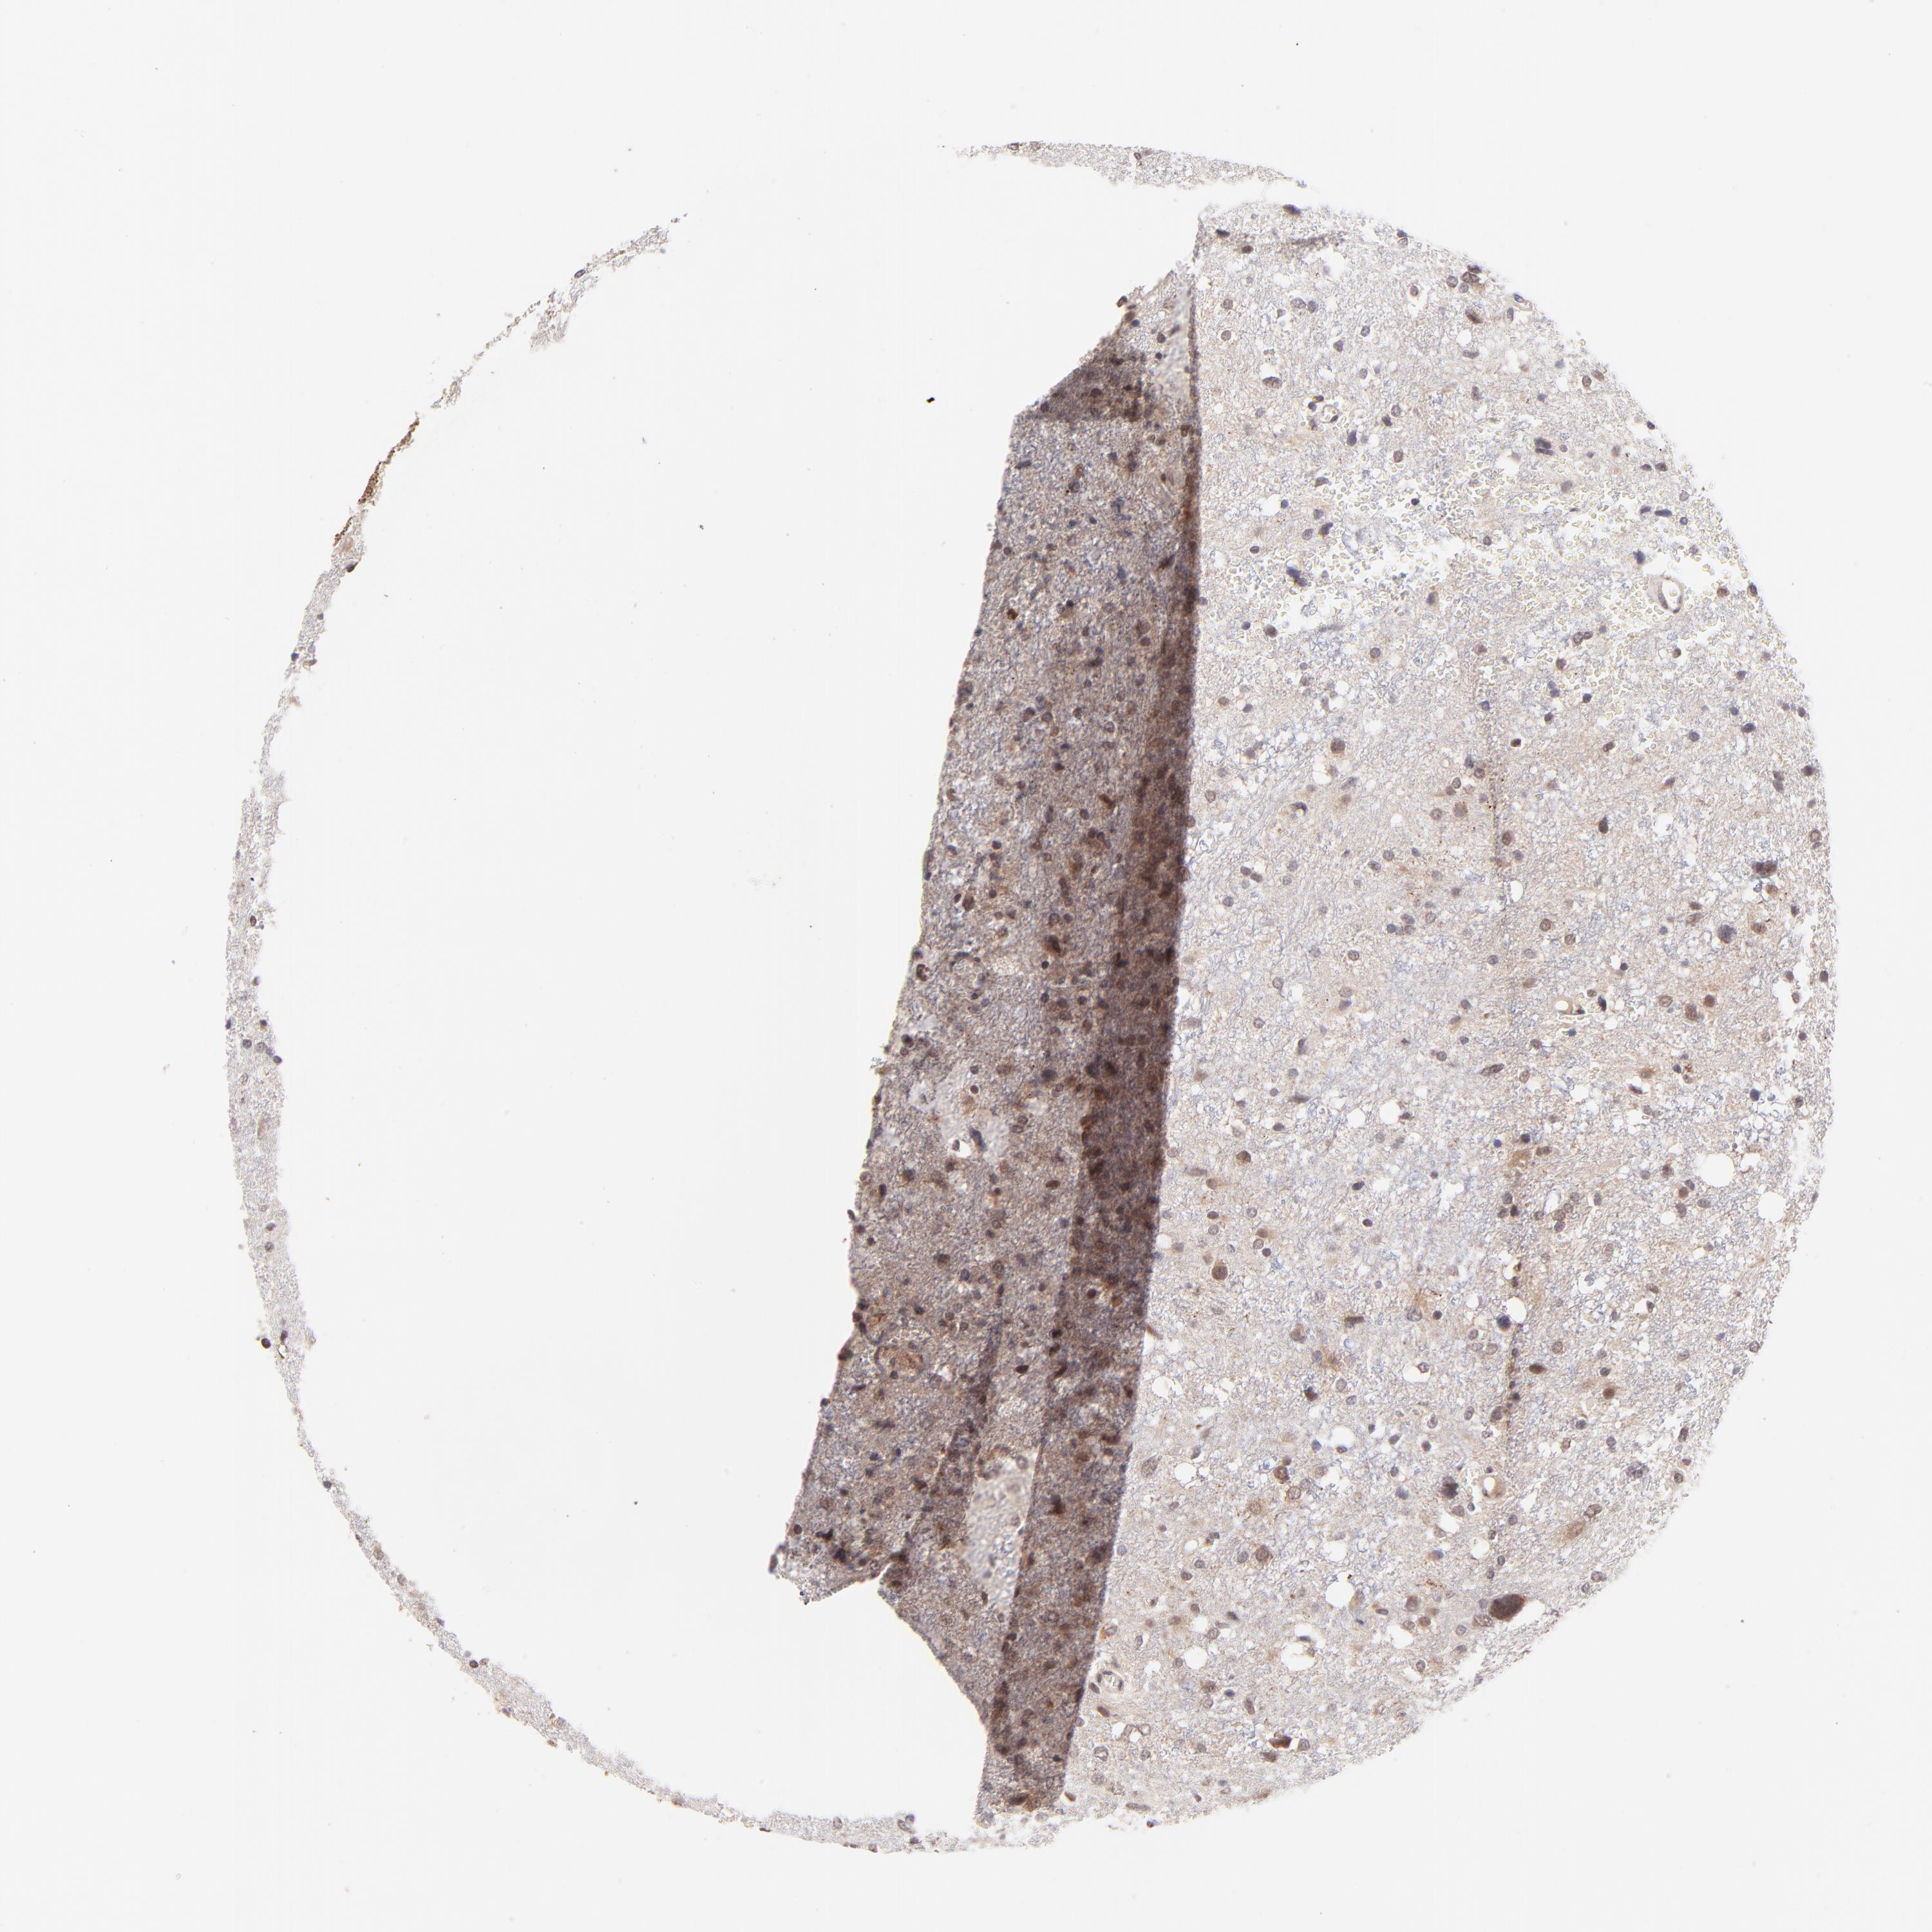

GLIOMA - Protein expressioni

A mouse-over function shows sample information and annotation data. Click on an image to view it in a full screen mode. Samples can be filtered based on level of antibody staining by selecting one or several of the following categories: high, medium, low and not detected. The assay and annotation is described here.

Note that samples used for immunohistochemistry by the Human Protein Atlas do not correspond to samples in the TCGA dataset.

Antibody stainingi

Antibody staining in the annotated cell types in the current human tissue is reported as not detected, low, medium, or high, based on conventional immunohistochemistry profiling in selected tissues. This score is based on the combination of the staining intensity and fraction of stained cells.

Each image is clickable and will lead to virtual microscopy that enables deeper exploration of all samples and also displays staining intensity scores, fraction scores and subcellular localization as well as patient and tissue information for each sample.

Antibody HPA003184

Antibody HPA003185

Staining

High

Medium

Low

Not detected

Intensity

Strong

Moderate

Weak

Negative

Quantity

>75%

75%-25%

<25%

None

Location

Nuclear

Cytoplasmic/membranous

Cytoplasmic/membranous,nuclear

Glioma, malignant, High grade

Glioma, malignant, Low grade

Glioma, malignant, NOS